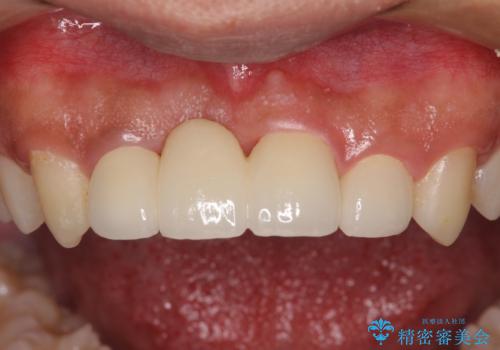

転んでぶつけて抜歯 前歯のオールセラミックブリッジ

- 酒席の後に転倒して前歯を損傷し、応急処置のみを受けてきたとのことで来院された患者様です。

損傷がひどく、前歯4本と広範囲であったため、症状やレントゲン写真、検査結果が一致せず、定期的に経過を見ながら診断していくこととしました。

右側前歯は歯根が短くなり、パンチング状に歯根に透過像が認められたため、予後不良と判断し抜歯することとしました。

当初のレントゲン写真では根尖部に骨透過像が認められた両サイドの2歯は、歯髄の正常な反応が認められたためそのまま保存し、左側前歯は歯髄が失活していたため根管治療を行うこととしました。

抜歯後の欠損部はブリッジにて補綴治療を行うこととしました。

事故直後のレントゲン写真では全ての歯の根尖部に骨透過像が認められましたが、治療後には全ての透過像がなくなっていました。

診断に2-3ヶ月かかりましたが、的確に診断を行うことができました。